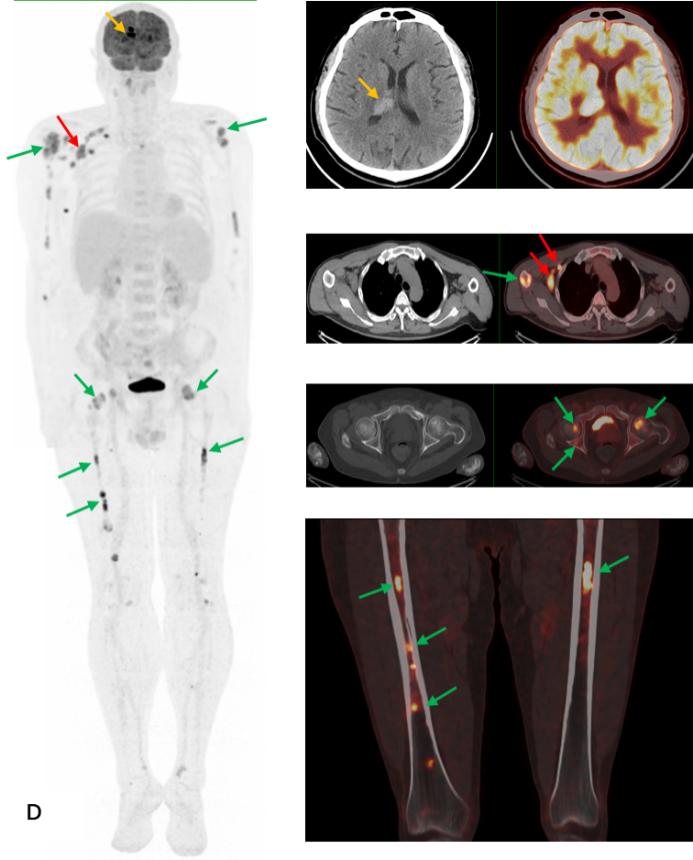

前列腺MRI示:前列腺移行帶結節狀異常信號,建議穿刺活檢;前列腺增生,PI-RADS2;雙側股骨頭信號異常,不排除轉移瘤(圖A)。為評估骨轉移情況遂行ECT全身骨顯像檢查,示:雙側肱骨頭、雙側股骨頭、右側前臂上段、右側股骨中下段代謝異常增強(圖B)。骨顯像不符合前列腺癌骨轉移典型表現,同時結合患者胸部CT(圖C)平掃示右側腋窩多發淋巴結腫大,生化檢查示乳酸脫氫酶620U/L(97-270),懷疑系血液系統腫瘤,建議患者行PET/CT檢查。PET/CT示:右側腦室內高密度灶,多發FDG代謝增高淋巴結及多發骨骼/骨髓FDG代謝增高灶,考慮淋巴瘤(圖D)。

PEC/CT檢查右側腦室內高密度灶(黃箭),多發FDG代謝增高淋巴結(紅箭)及多發骨骼/骨髓FDG代謝增高灶(綠箭),同機CT平掃示相應骨骼未見明顯破壞,考慮淋巴瘤。

患者后在局麻下行右胸壁下淋巴結切除活檢術,術后病理示:彌漫大B細胞淋巴瘤,生發中心來源。